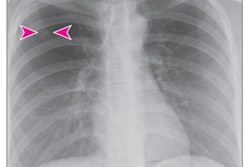

It's increasingly common for clinicians to find incidental pulmonary nodules in patients undergoing imaging for other indications, the group noted. And determining whether these nodules are malignant can be tricky.

Surprisingly, there's a lack of population-based research regarding incidental nodule characteristics and the likelihood of cancer. Clinicians use prediction models to try to determine malignancy risk: Two common ones are the Mayo Clinic Solitary Pulmonary Nodule Malignancy Risk model for incidental nodules and the Brock University Calculator for nodules detected on lung cancer screening.

Vachani's group addressed this question via a study that included data from 23,780 Kaiser Permanente Southern California patients with incidental pulmonary nodules measuring larger than 8 mm identified on chest CT between 2006 and 2016.